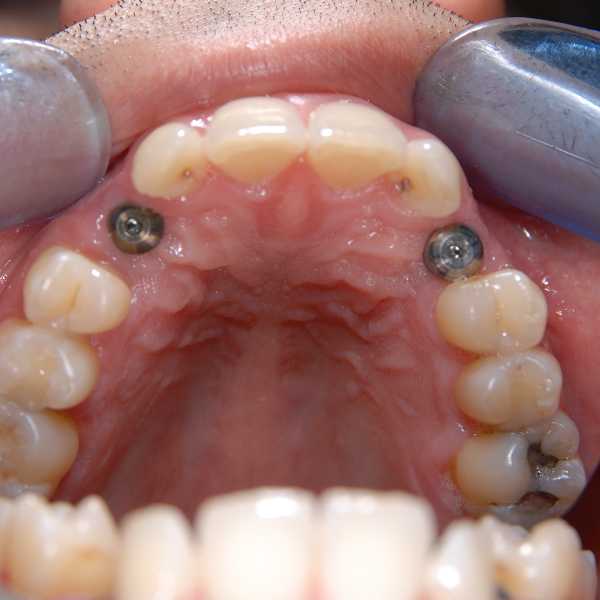

Pic 1 Implants replacing surgically removed canines from palate